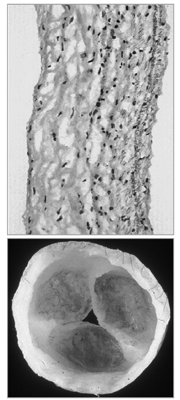

The valves of the heart cannot regenerate spontaneously. Therefore, heart valve disease generally necessitates surgical repair or replacement of the diseased tissue by mechanical or bioprosthetic valve substitutes in order to avoid potentially fatal cardiac or systemic consequences. Although survival and quality of life is enhanced for many patients treated surgically, currently available valve substitutes remain imperfect. This is especially the case in pediatric applications, where physiologically corrective procedures can be successfully performed, but reoperations are frequently required to replace failed valve substitutes or accommodate growth of the patient. While much work is currently underway to incrementally improve existing valve substitutes, a major impact will require radically new technologies, including tissue engineering or regeneration. The use of engineered tissue offers the potential to create a non-obstructive, non-thrombogenic tissue valve substitute containing living cells capable of providing ongoing remodeling and repair of cumulative injury to the extracellular matrix. Ideally, this would allow growth in maturing recipients. The innovative fabrication of materials and the development of sophisticated methods to repair or regenerate damaged or diseased heart valves requires integration of a diverse array of basic scientific principles and enabling technologies. Thus, heart valve tissue engineering requires an understanding of relationships of structure to function in normal and pathological valves (including mechanisms of embryological development, tissue repair and functional biomechanics), and the ability to control cell and tissue responses to injury, physical stimuli and biomaterial surfaces, through chemical, pharmacological, mechanical and potentially genetic manipulations. These approaches created by advances in cell biology raise exciting possibilities for in situ regeneration and repair of heart valves.